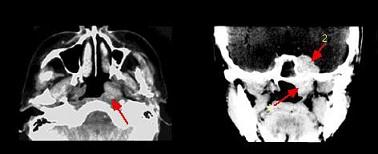

问题 哪项不符合腺样囊性癌的肿瘤(如组图)生物学行为()

选项 A.常出现神经症状 B.血行转移率高 C.区域淋巴结转移率高 D.肿瘤易沿神经生长 E.侵袭性极强

答案 C